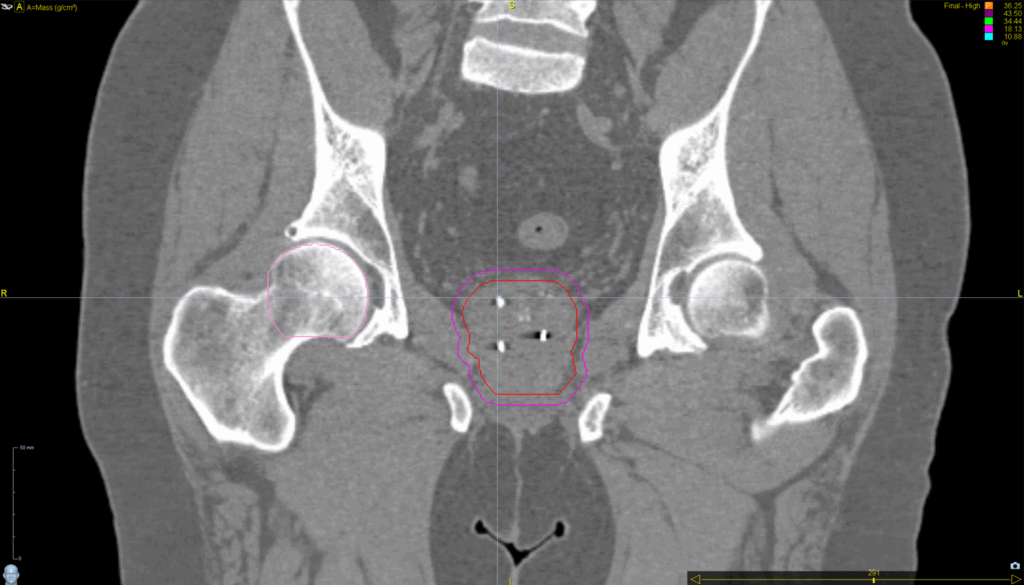

Planning CT Images